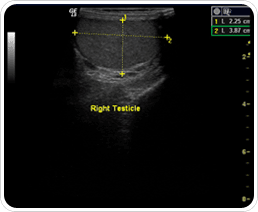

´Ù½Ã ¾ð±ÞÇϸé, °³Àκ° ¸ÂÃã½ÄÀ¸·Î ÀÎÁ¶ °íȯÀ» ÀÚ¿¬½º·´°Ô º¸À̵µ·Ï ¼ö¼úÀ» ÇØ¾ßµË´Ï´Ù. µû¶ó¼, º»¿ø¿¡¼´Â ÀÌÁ¡À» °í·ÁÇÏ¿© ¼ö¼úÀü¿¡ ÃÊÀ½ÆÄ °Ë»ç¸¦ ÅëÇØ¼ ¹Ý´ëÆí °íȯÀÇ Å©±â, ¸ð¾ç, À§Ä¡, À½³¶ÀÇ Á¿ì´ëεµ, ¿ÂµµÂ÷ÀÌ¿¡ ´ëÇÑ À½³¶ ÃÄÁüÁ¤µµµîÀ» ºÐ¼®ÇÏ¿© °³Àκ° ¸ÂÃãÀ¸·Î ÀÎÁ¶°íȯ»ðÀÔ¼ö¼úÀ» Àû¿ëÇϹǷÎ, ¼ö¼ú ÈÄ¿¡ ¸ð½ÀÀÌ ½ÇÁ¦ °íȯ°ú °¡Àå Èí»çÇÑ ÀÚ¿¬½º·¯¿î ¿Ï¼ºµµ ³ôÀº ¼ö¼ú°á°ú¸¦ °¡Á®¿Ã ¼ö ÀÖ½À´Ï´Ù

¹Ì¸® ¼ö¼ú Àü ÃÊÀ½ÆÄ °Ë»ç¸¦ ½ÃÇàÇÏ¿© ±âÁ¸¿¡ ÀÖ´Â °íȯ°ú ÀÎÁ¶°íȯÀÌ µé¾î°¥ ¹Ý´ëÆí À½³¶¿¡ ´ëÇÑ ¼ö¼úÁ¤º¸¸¦ ½Ê ¼ö³â°£ ÆÄ¾ÇÇÑ ÀÚ·á¿¡ ±Ù°ÅÇÏ¿© º»¿ø¸¸ÀÇ ¼ö¼ú °æÇè¿¡¼ ³ª¿À´Â ¹æ¹ýÀÔ´Ï´Ù.

¿ÞÂÊ »çÁøÀº ÀÎÁ¶ °íȯ »ðÀÔ¼úÀ» Çϱâ Àü¿¡ ¹Ý´ëÂÊ °íȯÀ» ÃÊÀ½ÆÄ °Ë»ç·Î ÃÔ¿µÇÑ »çÁøÀÔ´Ï´Ù. |